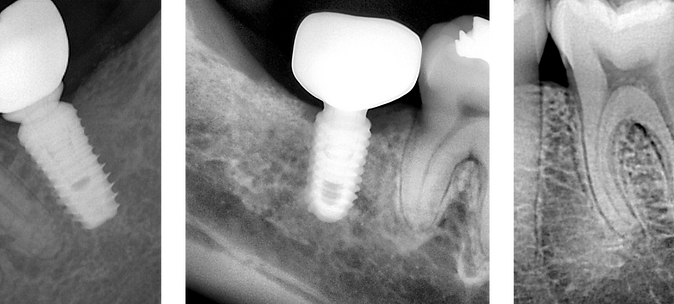

The X4 Handheld X-Ray from Mid America Dental Sales is designed to bring next-level efficiency and comfort to your operatory. Weighing in at just 4 pounds, this portable x-ray unit delivers serious imaging power without the bulk—making it ideal for implant procedures, pediatric care, and patients with limited mobility.

Built for safety as much as performance, the X4 features a protective scatter shield that exceeds 0.5 mm Pb lead equivalency, giving clinicians peace of mind during use. Its fixed 70kV/2mA beam and 0.4 mm focal spot produce high-quality diagnostic images, while the ergonomic design minimizes arm fatigue—especially important during long days or high-volume patient loads.

- Ideal for implants, pediatrics, and special patient needs